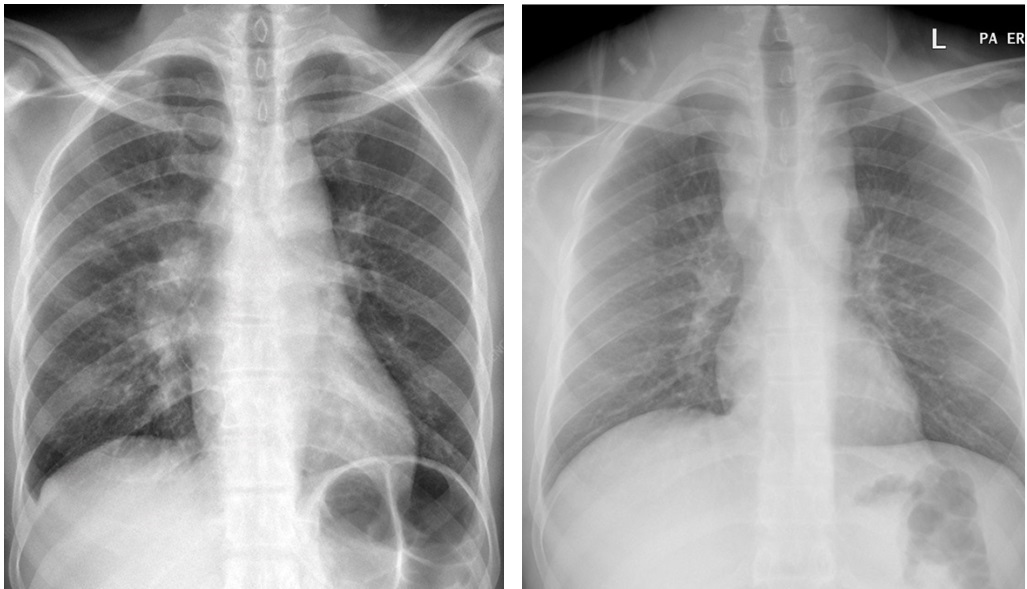

Рисунок 4. Милиарный туберкулез. А. Рентгенограмма грудной клетки, выполненная в период до 10 дней с момента манифестации заболевания. Билатерально ассиметрично за счет левосторонней латерализации отмечаются невыраженные неспецифические ретикулярные изменения без признаков визуализации паттерна диссеминации. Б. Рентгенограмма грудной клетки, выполненная через 2 недели от момента манифестации заболевания. Билатерально диффузно отмечаются множественные милиарные очаговые течения с нечеткими контурами и низкой интенсивностью с симметричностью распределения. Case courtesy of Zach Drew, Radiopaedia.org, rID: 75157